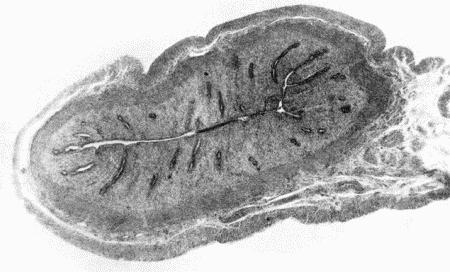

Патологоанатомические изменения соответствуют картине воспаления. Вначале наблюдаются гиперемия и серозно-клеточная инфильтрация интерстициальной ткани, а затем дегенеративные изменения клеток миокарда. При очаговых поражениях сердечная мышца на разрезе имеет пестрый вид, а при диффузном изменения распространяются равномерно по всему миокарду. Мышца сердца дряблая. Полости правого и левого желудочка расширены. Воспаление сердечной мышцы может сопровождаться кровоизлияниями (особенно при септических заболеваниях).